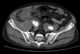

Ruptured aneurysm

An aneurysm is an outward bulging, likened to a bubble or balloon, caused by a localized, abnormal, weak spot on a blood vessel wall. Aneurysms may be a result of a hereditary condition or an acquired disease. [Source: Wikipedia ]